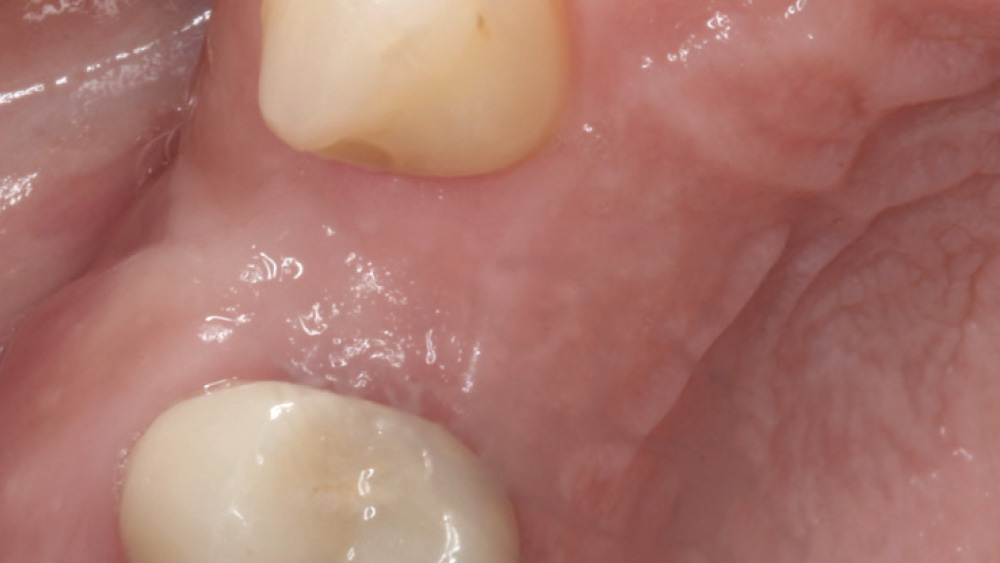

When the attached tissue is minimal, a flap procedure allows the surgeon to reposition the flap to create more attached gingiva and improve the interdental papillae at the implant site. Reflecting a gingival flap also enables the practitioner to more clearly see the final position of the implant at the crest of the bone. If it’s necessary to visualize the bone during the surgical procedure due to uncertain ridge width or height, flap reflection is the safest, most predictable approach.

• Flap can be repositioned to create more attached gingiva

The following case, which I performed alongside Dr. Stephanie Tilley of Pensacola, Florida, illustrates the use of both surgical techniques for the same patient, who presented with edentulous spaces in the areas of both right and left maxillary first bicuspids. Due to varying soft-tissue volume on each side of the arch, implant surgery was performed using a flapless procedure for one site, while the attached gingiva was reflected to expose the available hard tissue for the other. As a result of proper site evaluation, treatment planning and restorative-driven implant placement, both surgical techniques led to successful outcomes for the patient.